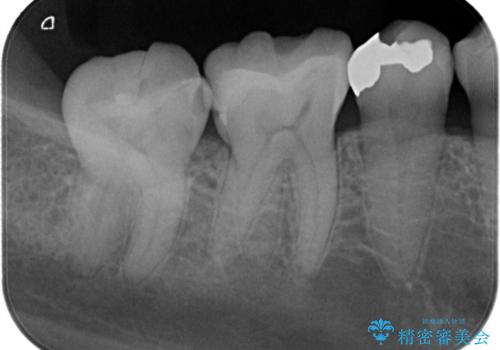

保険診療のCRインレーをセラミックインレーでやり直し

- 定期検診にて他院で治療された保険適用CRインレー部分(大臼歯2本)にむし歯を認めたため、セラミックインレーにて修復を行いました。

e-max プレスインレーにて修復治療を行っているため適合性及び審美性の高い治療を行うことができます